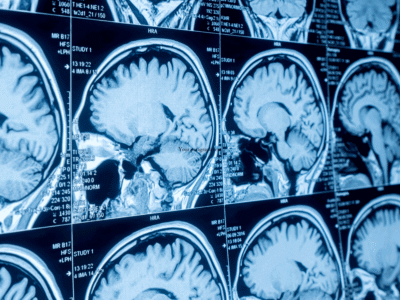

A brain scan.

Traumatic brain injury causes significant long-term problems. The human body has a remarkable capacity to recover, but brain tissue will not heal itself, and there are currently no medical treatments to regenerate damaged brain tissue.